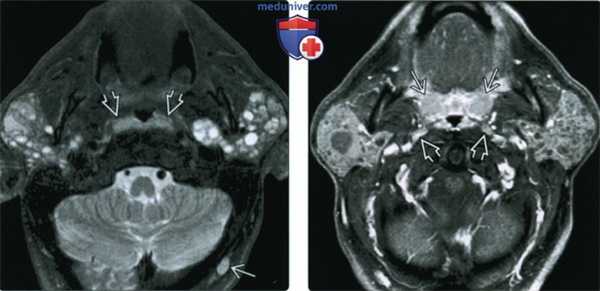

(Слева) Классическая картина доброкачественного лимфоэпителиального поражения околоушных желез при ВИЧ. В обеих околоушных железах обнаруживаются кистозные и солидные лимфоидные образования. Обратите внимание на гипертрофию лимфоидной ткани глоточной миндалины. Реактивная лимфаденопатия (здесь не показана) также весьма характерна для доброкачественного лимфоэпителиального поражения.

(Справа) КТ с КУ, аксиальная проекция. У ВИЧ-пациента в обеих околоушных железах (их плотность повышена) определяются множественные микрокисты. Такая картина характерна для доброкачественного лимфоэпителиальною поражения. Обратите внимание на гипертрофию глоточной миндалины. (Слева) КТ с КУ, аксиальная проекция. Крупные многокамерные кисты в обеих околоушных железах у пациента с ВИЧ. Внутри кисты видны перегородки.

(Слева) MPT STIR, аксиальная проекция. В обеих околоушных железах визуализируются лимфоэпителиальные кисты. Обратите внимание, что вовлечены и поверхностная, и глубокая доли желез. Присутствует реактивная лимфаденопатия затылочных узлов. Гипертрофия небных миндалин незначительная.

(Справа) МРТ Т1ВИ FS c КУ, аксиальная проекция. Двусторонние кистозные и солидные образования у ВИЧ-положительного пациента. Небные миндалины гипетрофированы, также имеет место реактивная лимфаденопатия латеральных заглоточных лимфоузлов.

(Слева) На аксиальной MPT (Т2 FS) в обеих околоушных железах определяются объемные образования с сигналом высокой интенсивности. И солидные, и кистозные ДЛЭП характеризуются гиперинтенсивным Т2 сигналом. Обратите внимание на увеличение глоточных миндалин.

(Справа) На аксиальной МРТ (Т1 С+) визуализируются объемные образования в обеих околоушных железах с контрастирующимся «ободком». Солидные ДЛЭП сложнее выявить на исследованиях с контрастом из-за «смешивания» контрастирующихся участков с жировой тканью околоушной железы.